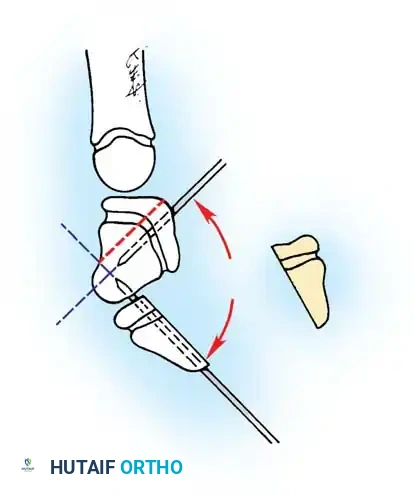

- Inspect the FDS tendon for a more proximal-than-normal decussation (chiasm of Camper) or an abnormal insertion into the FDP tendon.

- If an abnormal FDS slip is tethering the FDP, excise one or both slips of the FDS tendon to decompress the sheath.

- Inspect the A3 pulley. If triggering occurs at this level, carefully release the A3 pulley, ensuring the A2 and A4 pulleys remain strictly intact.

Biomechanical illustration showing the relationship of the FDS and FDP tendons within the digital sheath.

A severe subgroup described by Koman, Toby, and Poehling involves severe PIP flexion deformities present at birth, often affecting multiple digits without a predilection for the small finger. This subtype is heavily driven by extensor mechanism pathology (attenuation of the central slip, palmar subluxation of lateral bands).

Smith emphasized a "unifying theory" of camptodactyly, advocating that all abnormal structures must be systematically addressed. The frequency of involvement includes skin (100%), FDS (66%), retinaculum cutis (55%), and lumbricals (22%).